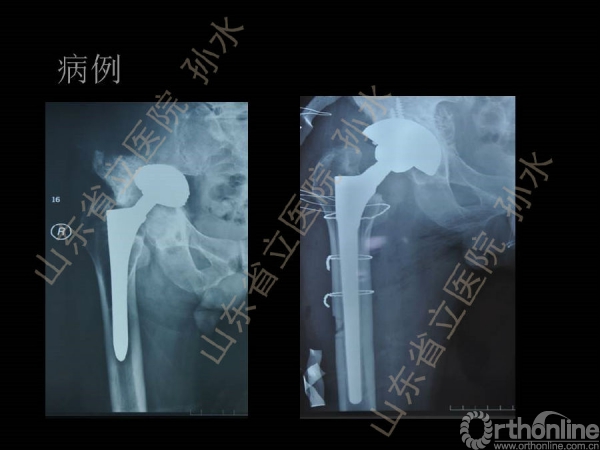

孙水:Jumbo-Cup在髋关节翻修中的应用